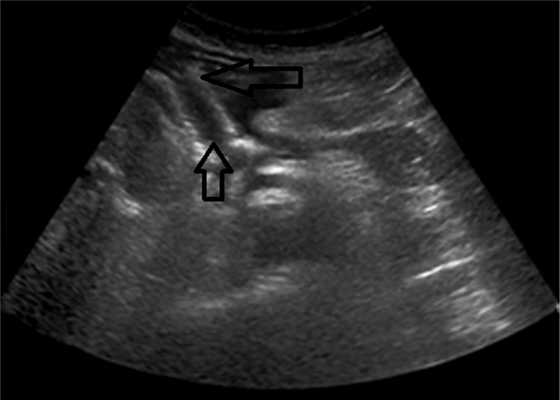

Контрольное УЗИ, выполненное перед выпиской, выявило отсутствие жидкостного образования у 18 (81,9%) пациентов, у 4 (18,2%) — уменьшение полости ПК более чем в 2 раза (рис. 3). Рис. 3. Стент в области головки поджелудочной железы, полость отсутствует, стрелками указаны края стента (изображение при ультразвуковом исследовании).